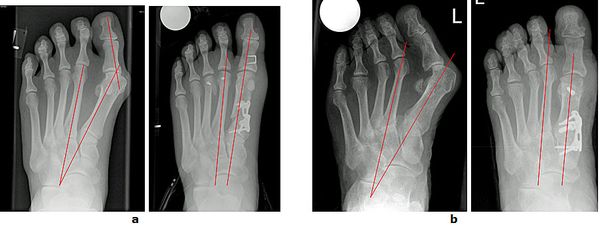

Abb.3: a Korrektur einer mittelschweren Hallux valgus Fehlstellung durch eine Basisosteotomie.

b Korrektur einer schweren Hallux valgus Fehlstellung mit luxierten Krallenzehen und chronischer Metatarsalgie durch eine Lapidus Arthrodese. Mit dieser Technik können selbst hochgradige Fehlstellungen begradigt werden. Bei beiden Techniken wird der Knochen wird mit einer winkelstabilen Platte fixiert. Dies bietet ein höchstes Maß an Stabilität und ermöglicht die sofortige postoperative Belastung.